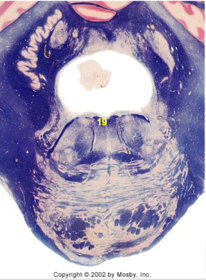

| Spinal tract of V | |

| Spinal nucleus of V | |

| Medial vestibular nucleus | |

| Inferior vestibular nucleus | |

| Dorsal cochlear nucleus | |

| Ventral cochlear nucleus | |

| Inferior olivary complex | |

| Inferior cerebellar peduncle | |

| CN IX | |

| Anterior spinocerebellar tract | |

| Central tegmental tract | |

| Olivary internal arcuate fibers | |

| Solitary tract | |

| Abducens root fibers | |

| Longitudinal pontine fibers (corticospinal tract) | |

| Transverse pontine fibers (dark fibers) | |

| Pontine nuclei (pale) | |

| Medial lemniscus | |

| ALS | |

| Trapezoid body | |

| Ventral trigeminothalamic tract | |

| Superior olive | |